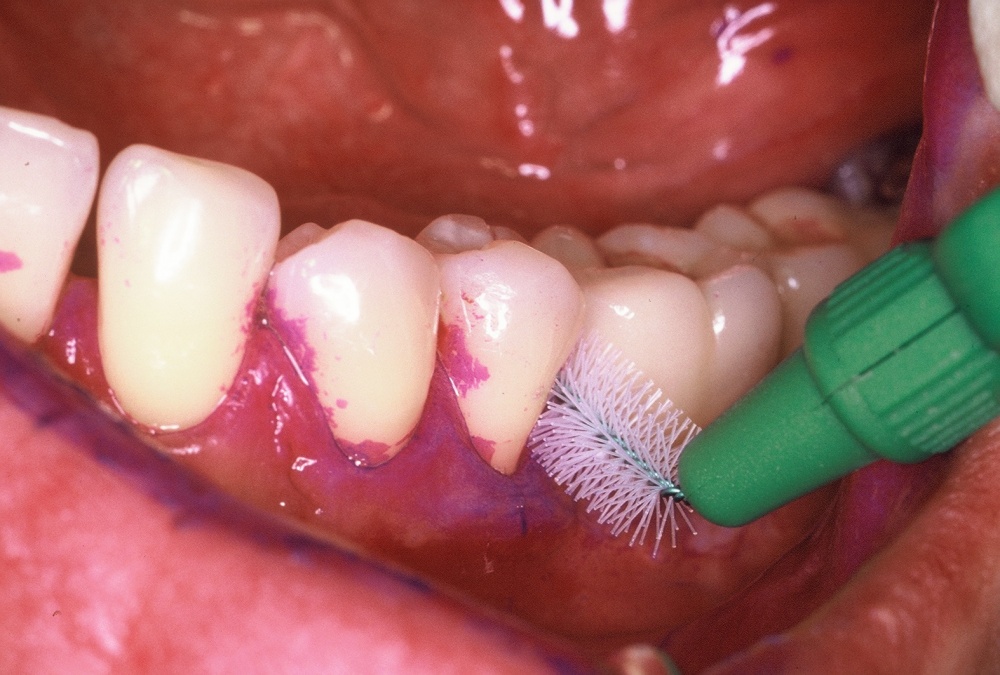

•IP1 – Mundhygienestatus: Darunter versteht man die Beurteilung der Mundhygiene mittels Anfärben der bakteriellen Beläge und der Benutzung eines geeigneten Index, z. B. des Approximalraumplaqueindex (Abb. 6). Für die Beurteilung des Gingivazustandes ist ebenfalls ein geeigneter Index anzuwenden, z. B. der Sulkusblutungsindex.

•IP2 – Mundgesundheitsaufklärung: Darunter versteht man die Aufklärung des Patienten über die Krankheitsursachen von Karies und Parodontalerkrankungen sowie deren Vermeidung. Darüber hinaus werden Ernährungshinweise gegeben und es erfolgt eine Mundhygieneberatung mit praktischen Übungen, z. B. der Interdentalhygiene.